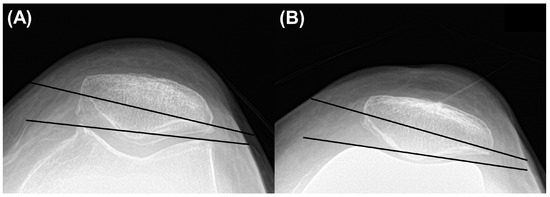

The patellar tilt angle was measured the angle between the line drawing the anterior limits of the femoral components or condyles and the line from one corner of the patella to the other on knee Merchant view. A positive value meant lateral translation of patella [24] (Figure 3).

Figure 3.

Measurement of (A) preoperative and (B) postoperative patellar tilt angle.